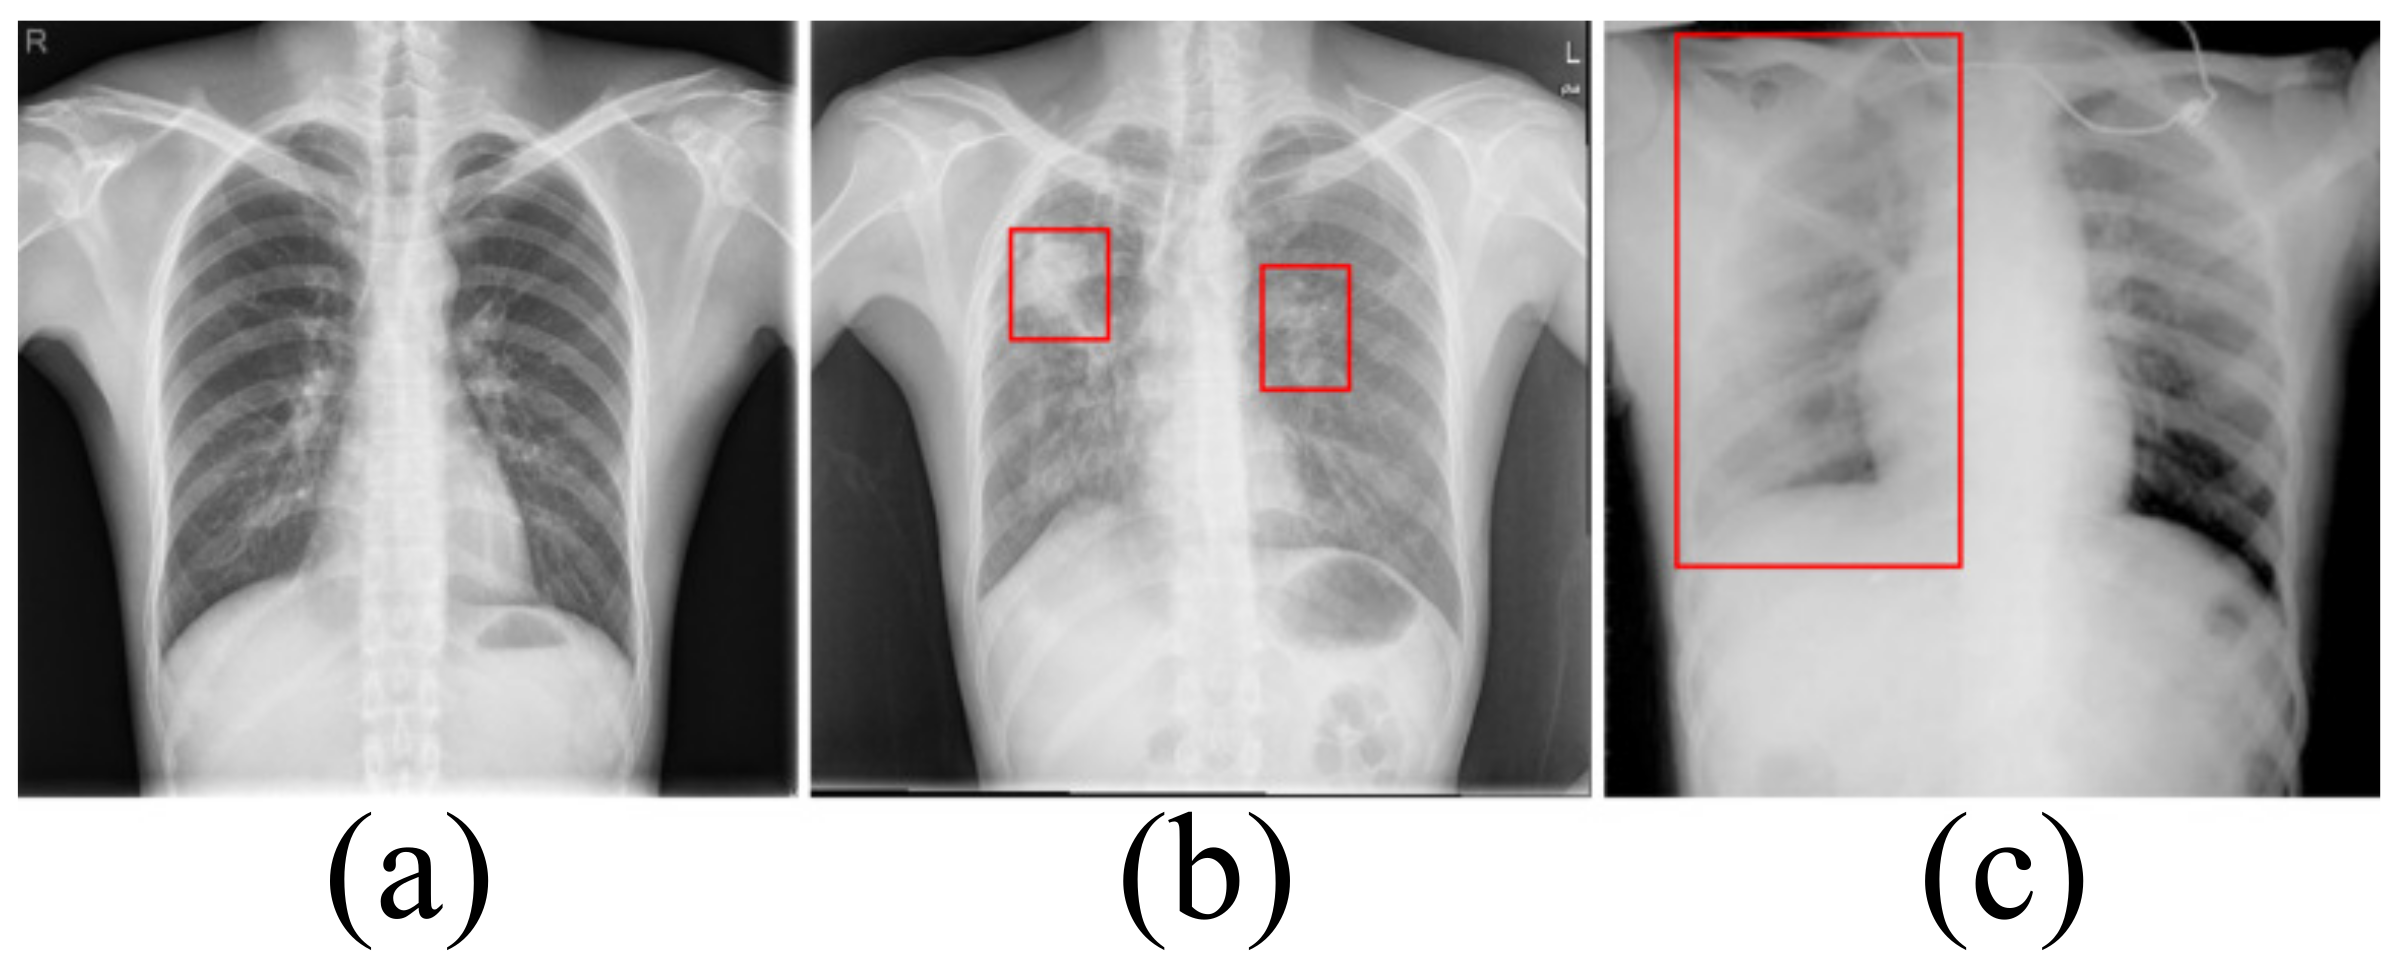

Accurately segmenting the lungs is a challenging image processing task [12]. The lungs have a strong transmittance to X-rays, and the gray value in the corresponding area of CXR is low. The surrounding tissues have low transmittance to X-rays and the gray value in the corresponding area of CXR is high. Figure 1 lists the CXRs of healthy people, patients with a small number of opacities and patients with a large number of opacities. In healthy people’s CXRs, the boundary between the lung and the surrounding tissues is obvious, clear and prominent. There are slight opacities in the lungs of CXRs in patients with a small number of opacities, especially at the edges of the lungs. The slight opacities reduce the contrast between the edge of the lung and the surrounding tissues and make segmentation difficult. For CXRs in patients with a large number of opacities, the boundary between the lungs and surrounding tissues is blurred. To a large extent, it is necessary to rely on the rich experience of physicians to correctly segment the lungs.

Figure 1.

(a) The chest X-ray image for healthy people. (b) The chest X-ray image in patients with a small number of opacities. (c) The chest X-ray image in patients with a large number of opacities.